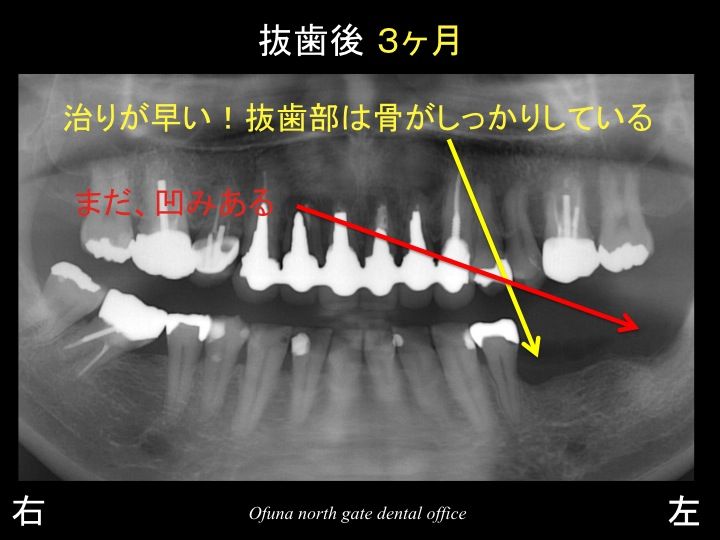

以下が抜歯後3ヶ月です。

他歯科医院で抜歯した一番奥の歯と

当医院で後から抜歯した手前の部分では、骨の再生が大きく違うのが分かるかと思います。

奥の方はまだ抜歯した凹みがありますが、

手前の方は骨が平坦に治っているのが分かると思います。

このレントゲンでは分からないのですが、

一番奥の部位は、骨の幅が非常に狭いのです。

これは、抜歯前の状態も悪かったのかもしれませんが、

ソケットプリザベーション法 を行っていなかったのも骨の回復が悪いことの一つになります。